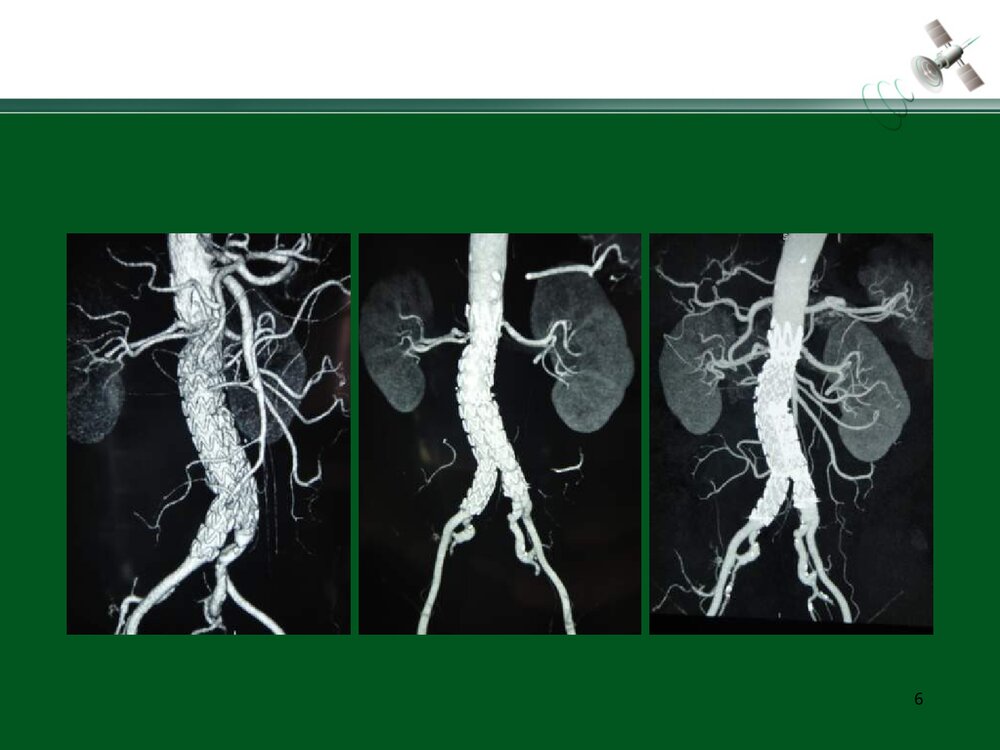

复杂腹主动脉瘤的腔内治疗常光其王深明教育部国家重点学科卫计委国家临床重点专科中山大学附属第一医院血管外科中山大学血管外科研究中心1复杂瘤颈AAA的腔内治疗复杂瘤颈指下列情况1.瘤颈长度小于15mm;2.瘤颈角度大于60度;3.瘤颈直径过大或过小(小于18mm或大于32mm)例1:短瘤颈AAA的EVAR3456例2:短瘤颈伴入路血管狭窄AAA的EVAR7891011例3:瘤颈狭窄且成角大于60度AAA的EVAR12131415161718192021例4:瘤颈成角大于60度AAA的EVAR2223242526例5:瘤颈成角伴腹主动脉分叉狭窄AAA的EVAR272829303132复杂入路AAA的腔内治疗复杂入路是指下列情况:(1)髂动脉弯曲成角超过90°;(2)双侧髂股动脉广泛钙化伴严重狭窄,直径小于7mm;(3)双侧髂股动脉闭塞例6:入路血管严重狭窄AAA的EVAR34353637383940例7:入路血管严重...